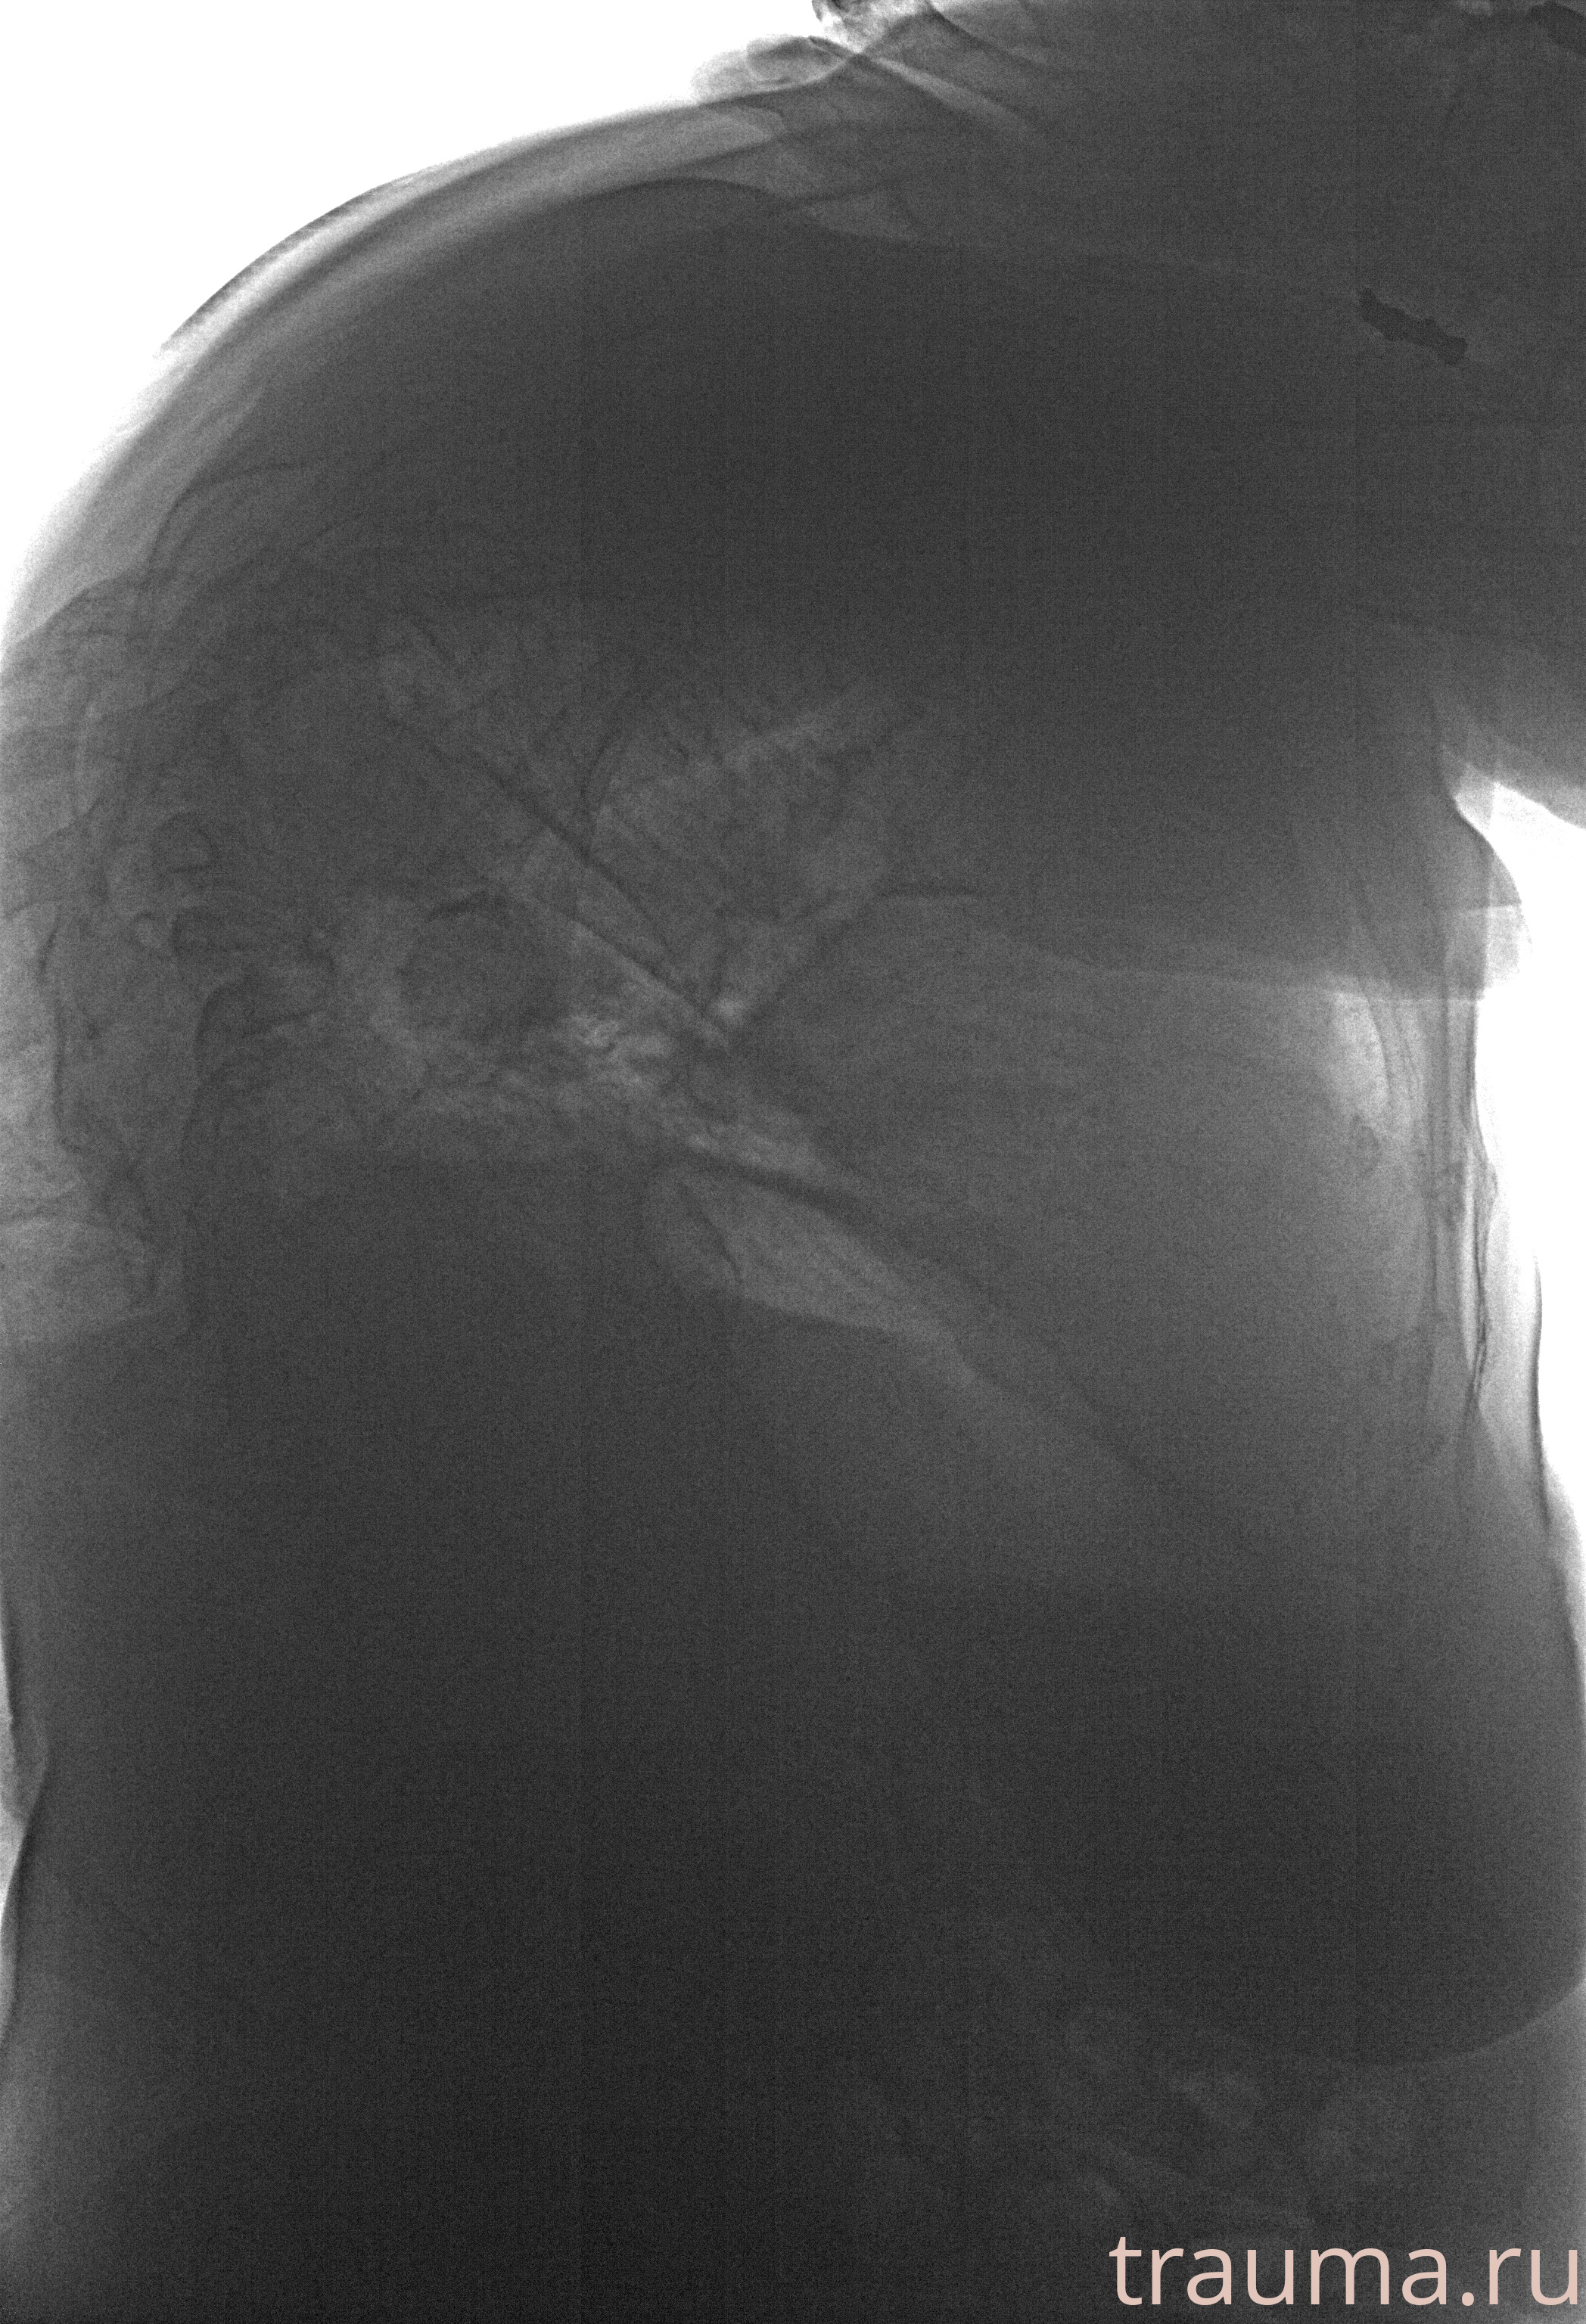

Рентгенограммы

Рентген на дому: по вашему адресу приезжает врач-рентгенолог, травматолог-ортопед с мобильным рентгеновским аппаратом, проводит диагностику травмы или заболевания, делает необходимые рентгенограммы, дает рекомендации по дальнейшему лечению. Получить качественные снимки в домашних условиях возможно благодаря уникальной методике, разработанной МосРентген Центром для института  Склифосовского

при переломе шейки бедра и пневмонии от компании МосРентген Центр - партнера Института имени Склифосовского